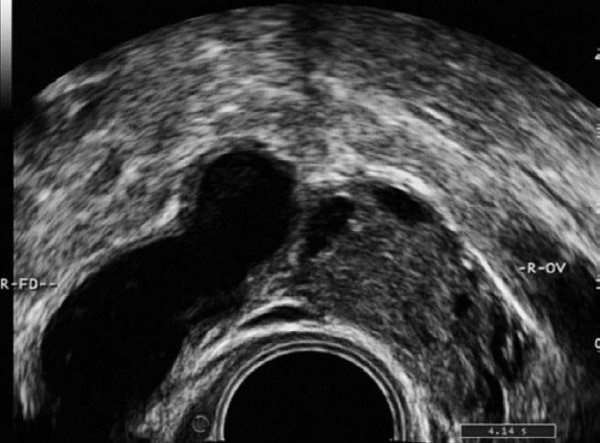

患者,女,30岁。婚后4年不孕,月经规则,曾有盆腔炎史,因下腹部坠胀、疼痛、来院诊治。超声检查报告显示:子宫后位,形态大小正常,肌壁回声均匀,内膜0.7cm,宫腔内未见明显异常。右卵巢大小4.6×2.5cm,左卵巢大小4.8×2.7cm,双附件区未见明确异常回声。盆腔内见游离液体,彩色血流未见异常。

超声提示:双侧卵巢测值偏大,盆腔积液